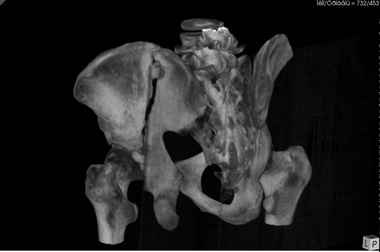

Уважаемые коллеги! В даном конкретном случае речь идет о "ложном суставе", поэтому показано реконструктивно-восстанвоительная операция т.е. остеотомия по линии "ложного сустава" затем остеосинтез реконструктивными пластинами, мы выбрали пахово-подвздошный (с наружным) доступ т.к. линия излома проходит на крышу вертлужной впадины. С уважением Ерсин Жунусов

Всем привет!

Андрей, на 3d снимках не видно соотношение суставных поверхностей, величину диастаза в ложном суставе и состояние головки (может уже протез нужен).

Если конгруэнтность и покрытие неплохие надо добиться сращения без репозиции (это тоже не просто, т.к. мышцы будут раскачивать крыло и ломать конструкции).

Если покрытие или конгруэнтность плохие а головка хорошая самое оптимальное - реконструкция свода и фиксация крыла без репозиции.